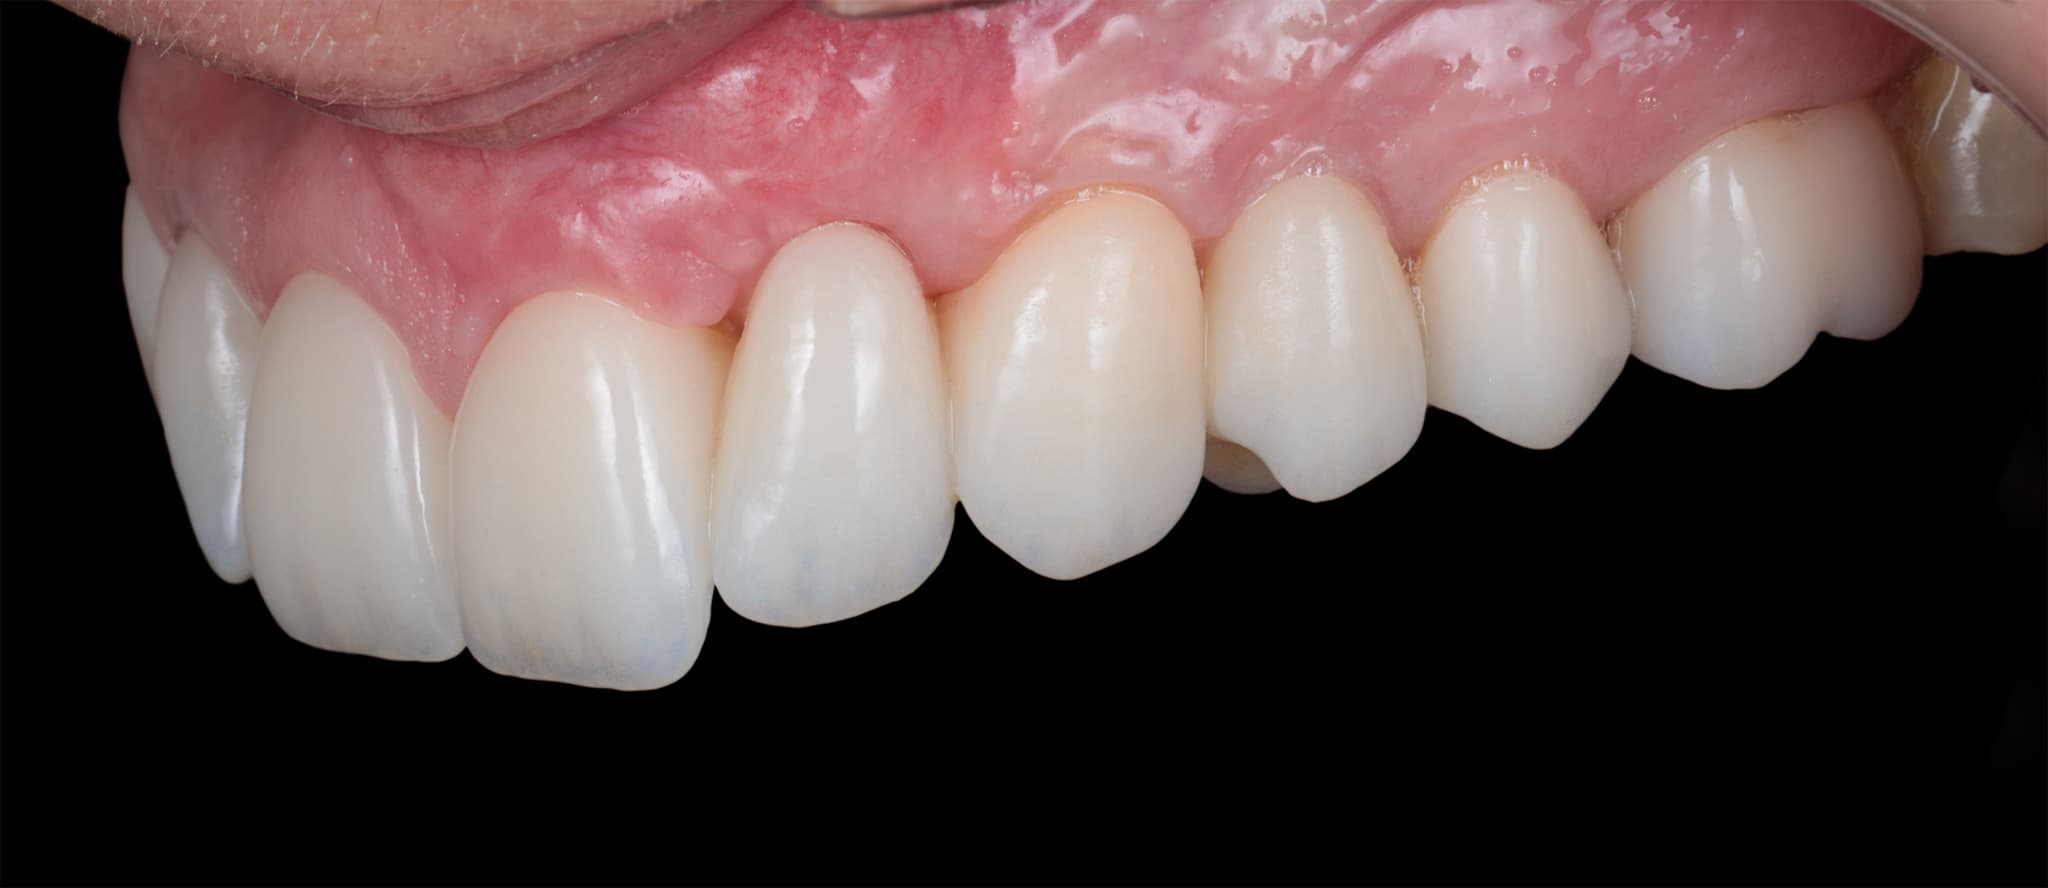

Healthy tissue supports natural esthetics.

Esthetic outcomes don’t just depend on ceramics—they rely on soft tissue health and contour. That’s why we consider periodontal architecture during the design phase. We shape, protect, and maintain soft tissue to support both health and harmony.